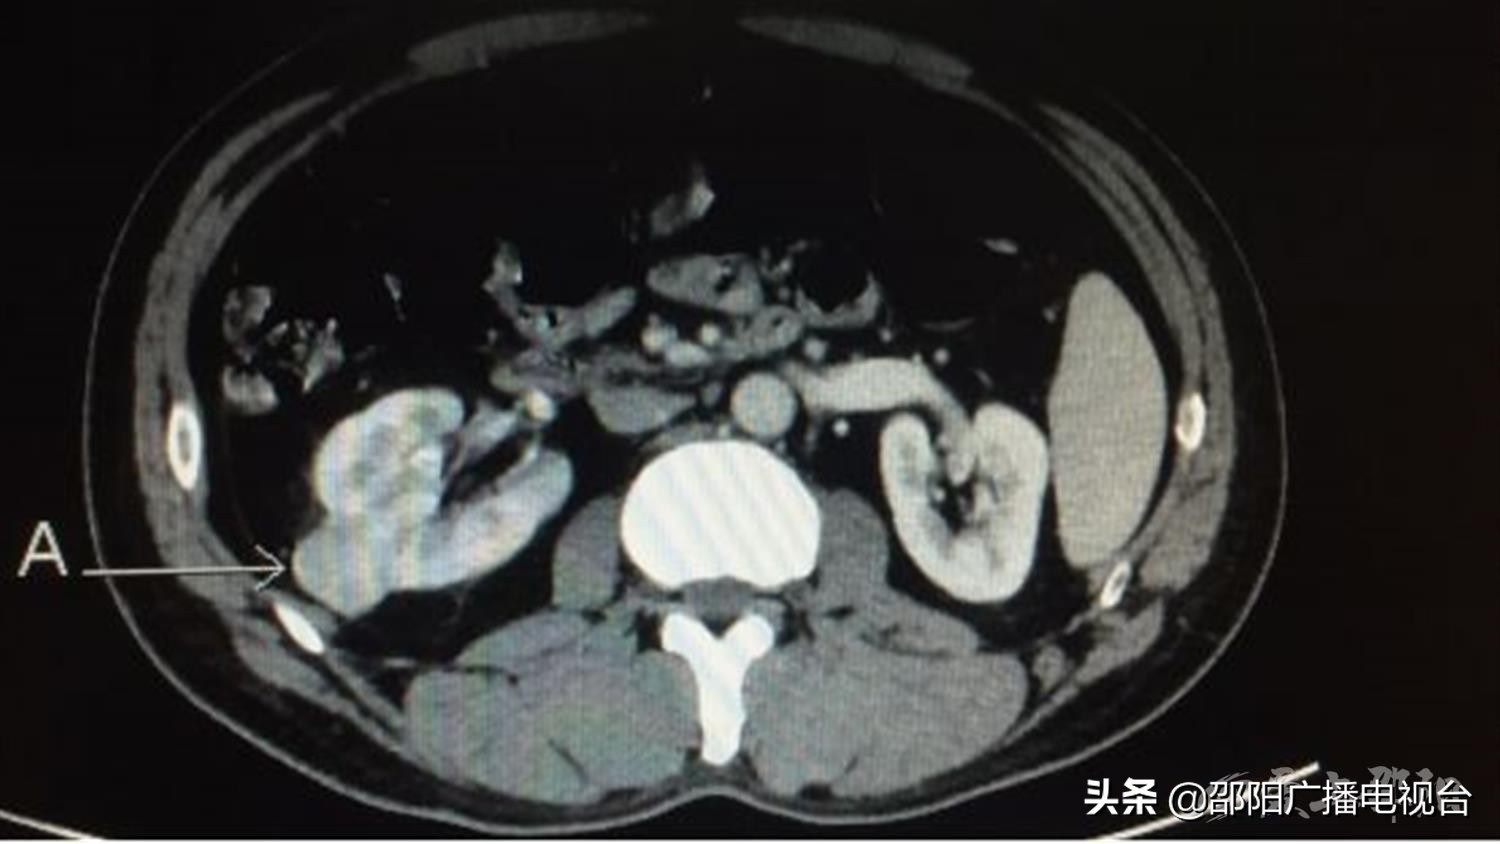

前段时间,王先生体检时超声发现右肾占位,来到我院泌尿外科治疗。术前CT提示右肾占位(26×28mm),考虑恶性肿瘤可能性大。手术团队根据术前检查准备了经腹腔及经后腹腔两套手术方案,科主任龙永福教授结合肿瘤位于背外侧的特点,认为后腹腔镜保留肾单位手术相较经腹腔途径更加直接和简易。

肿瘤(26×28mm)位于右肾背外侧

手术中发现肿瘤位于右肾背外侧,充分显露肿瘤后用血管夹阻断肾动脉,由浅入深逐步将肿瘤完整切除并缝合右肾集合系统及实质,右肾热缺血时间约25分钟,术中出血少于30ml,术后病理肾嫌色细胞癌。术后按照ERAS,患者早期进食、拔除尿管及引流管,术后第2日侧卧位和半坐位,术后第5日下床活动并顺利按时出院。